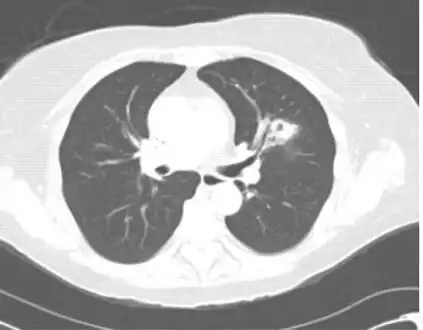

Chest computed tomography image showing left upper lobe cavitary lesion consistent with invasive pulmonary aspergillosis

Pulmonary aspergillosis